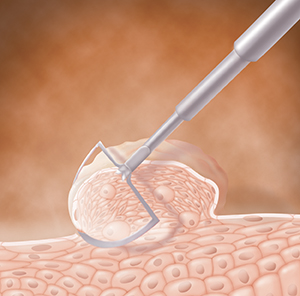

Wart removal

Warts can be removed in many ways. These include freezing, heat (cautery), lasers, and surgery. These procedures are done by your regular healthcare provider or a specialist. Before treatment, you may be given local anesthesia to numb the area. The number of treatments depends on how many warts are being removed. Your healthcare provider can give you more details.